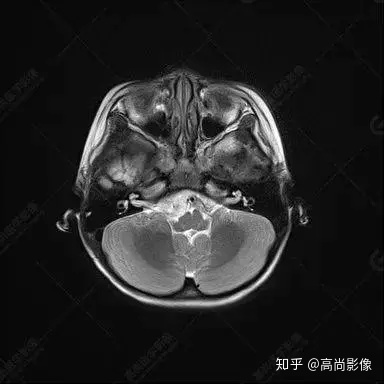

右側(cè)顳葉腫瘤切除術(shù)后(具體不詳):右側(cè)顳部骨質(zhì)不連續(xù)呈術(shù)后改變,右側(cè)顳葉術(shù)區(qū)見片狀長T1長T2信號影,F(xiàn)LAIR呈低信號;術(shù)區(qū)后方右側(cè)顳枕葉見一巨大占位性病變影,邊界欠清,大小約6.2×5.8×4.3cm(前后×左右×上下),信號不均勻,T1WI呈等稍低信號間雜少許高信號,T2WI呈高稍低混雜信號,DWI示部分病灶彌散受限,相應(yīng)ADC圖減低,磁敏感序列見部分呈極低信號,增強(qiáng)掃描可見明顯不均勻強(qiáng)化,鄰近硬腦膜及小腦幕增厚并明顯強(qiáng)化;另延髓右前方及右側(cè)橋小腦角區(qū)見一不規(guī)則形異常信號影,大小約3.2×1.3×3.7cm(左右×前后×上下),呈長T1稍長T2信號,F(xiàn)LAIR呈等信號,DWI未見受限,增強(qiáng)后明顯均勻強(qiáng)化,鄰近腦膜明顯強(qiáng)化。鄰近腦實質(zhì)及右側(cè)顳角明顯受壓;左側(cè)大腦半球未見局灶性信號異常,中線結(jié)構(gòu)稍左移。

右側(cè)顳葉腫瘤切除術(shù)后:現(xiàn)術(shù)區(qū)后方右側(cè)顳枕葉及延髓右前方占位,右側(cè)顳枕部硬腦膜及小腦幕明顯強(qiáng)化,結(jié)合既往影像資料,考慮為胚胎源性惡性腫瘤,如非典型畸胎樣/橫紋肌樣瘤(AT/RT)或原始神經(jīng)外胚層腫瘤(PNET)。

非典型畸胎樣/橫紋肌樣瘤(AT/RT) 是一種高度惡性中樞神經(jīng)系統(tǒng)腫瘤,臨床罕見,臨床表現(xiàn)無特異性,好發(fā)于 5 歲以下兒童,尤以 3 歲以下多見,在兒童原發(fā)性中樞神經(jīng)系統(tǒng)(CNS)腫瘤中占 1%~3%。該腫瘤體積一般較大,幕上大于幕下,有明顯的占位效應(yīng)。該腫瘤成分復(fù)雜,囊變、出血、壞死常見。因此 AT/RT信號混雜,囊性部分呈 T1WI低、T2WI高信號,增強(qiáng)后不強(qiáng)化;若瘤體出血,囊內(nèi)可見T1WI稍高信號、T2WI低信號,實性部分在 T1WI上呈混雜等、低信號,在T2WI 及 T2-FLAIR上呈混雜等高信號,增強(qiáng)掃描后大部分呈環(huán)形條帶樣明顯強(qiáng)化,中心壞死區(qū)不強(qiáng)化。另外,該腫瘤實性成分在DWI上呈高信號,說明腫瘤細(xì)胞核密集,水分子擴(kuò)散明顯受限,提示該腫瘤惡性程度高,容易復(fù)發(fā)及轉(zhuǎn)移。